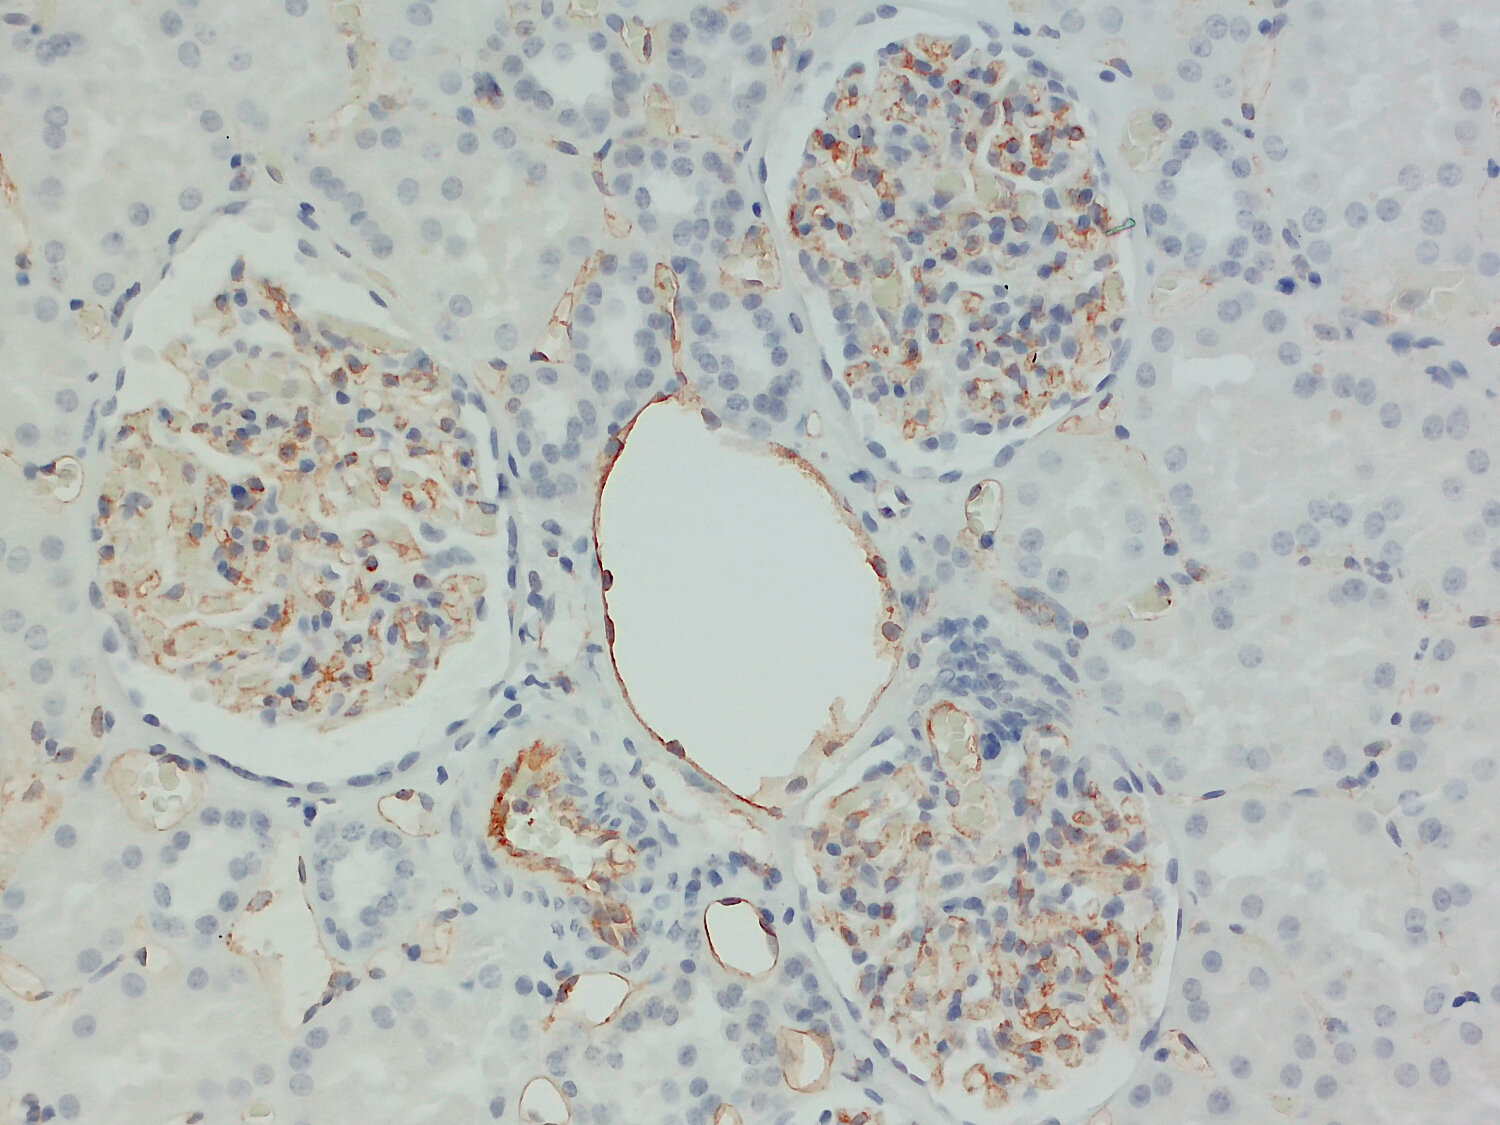

IHC-P: 1 : 1000 gallery

Immunohistochemistry (IHC-P) of formalin fixed, paraffin embedded (FFPE) tissue (some antibodies require special antigen retrieval steps, please refer to the ”Remarks” section). Immunoreactivity is usually revealed by fluorescence or a chromogenic substrate.

Immunodetection of CD31-positive endothelial cells (red) and Cytokeratin7-positive trophoblasts (green) in a human FFPE placenta section.

CD31 or platelet/endothelial cell adhesion molecule-1 (PECAM-1) is a cell adhesion molecule that contains a single trans-membrane domain and 6 Ig-like C2-type (immunoglobulin-like) domains (1). It is expressed on the surface of leukocytes and platelets and is primarily concentrated at endothelial cell-cell junctions (2). CD31 plays a role in several important biological processes, such as vascular development, maintenance of vascular endothelial barrier function and leukocyte emigration at inflammatory sites. In addition, CD31 promotes cancer metastasis by inducing epithelial-mesenchymal transition (3).